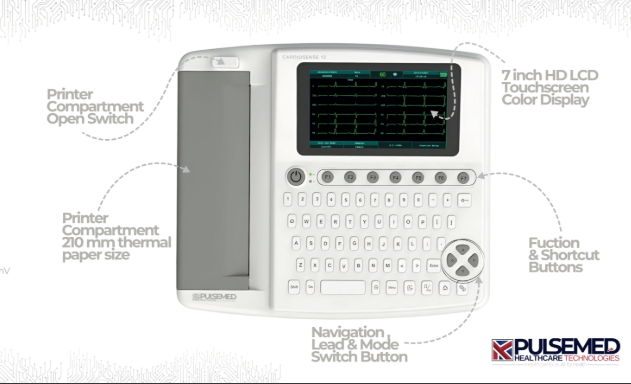

Pulsemed UK Cardiosense 12

Pulsemed UK Cardiosense 12

3 Channel 7 Inch Touch Screen Portable Electrocardiograph ECG Machine

3 Channel 7 Inch Touch Screen Portable Electrocardiograph ECG Machine